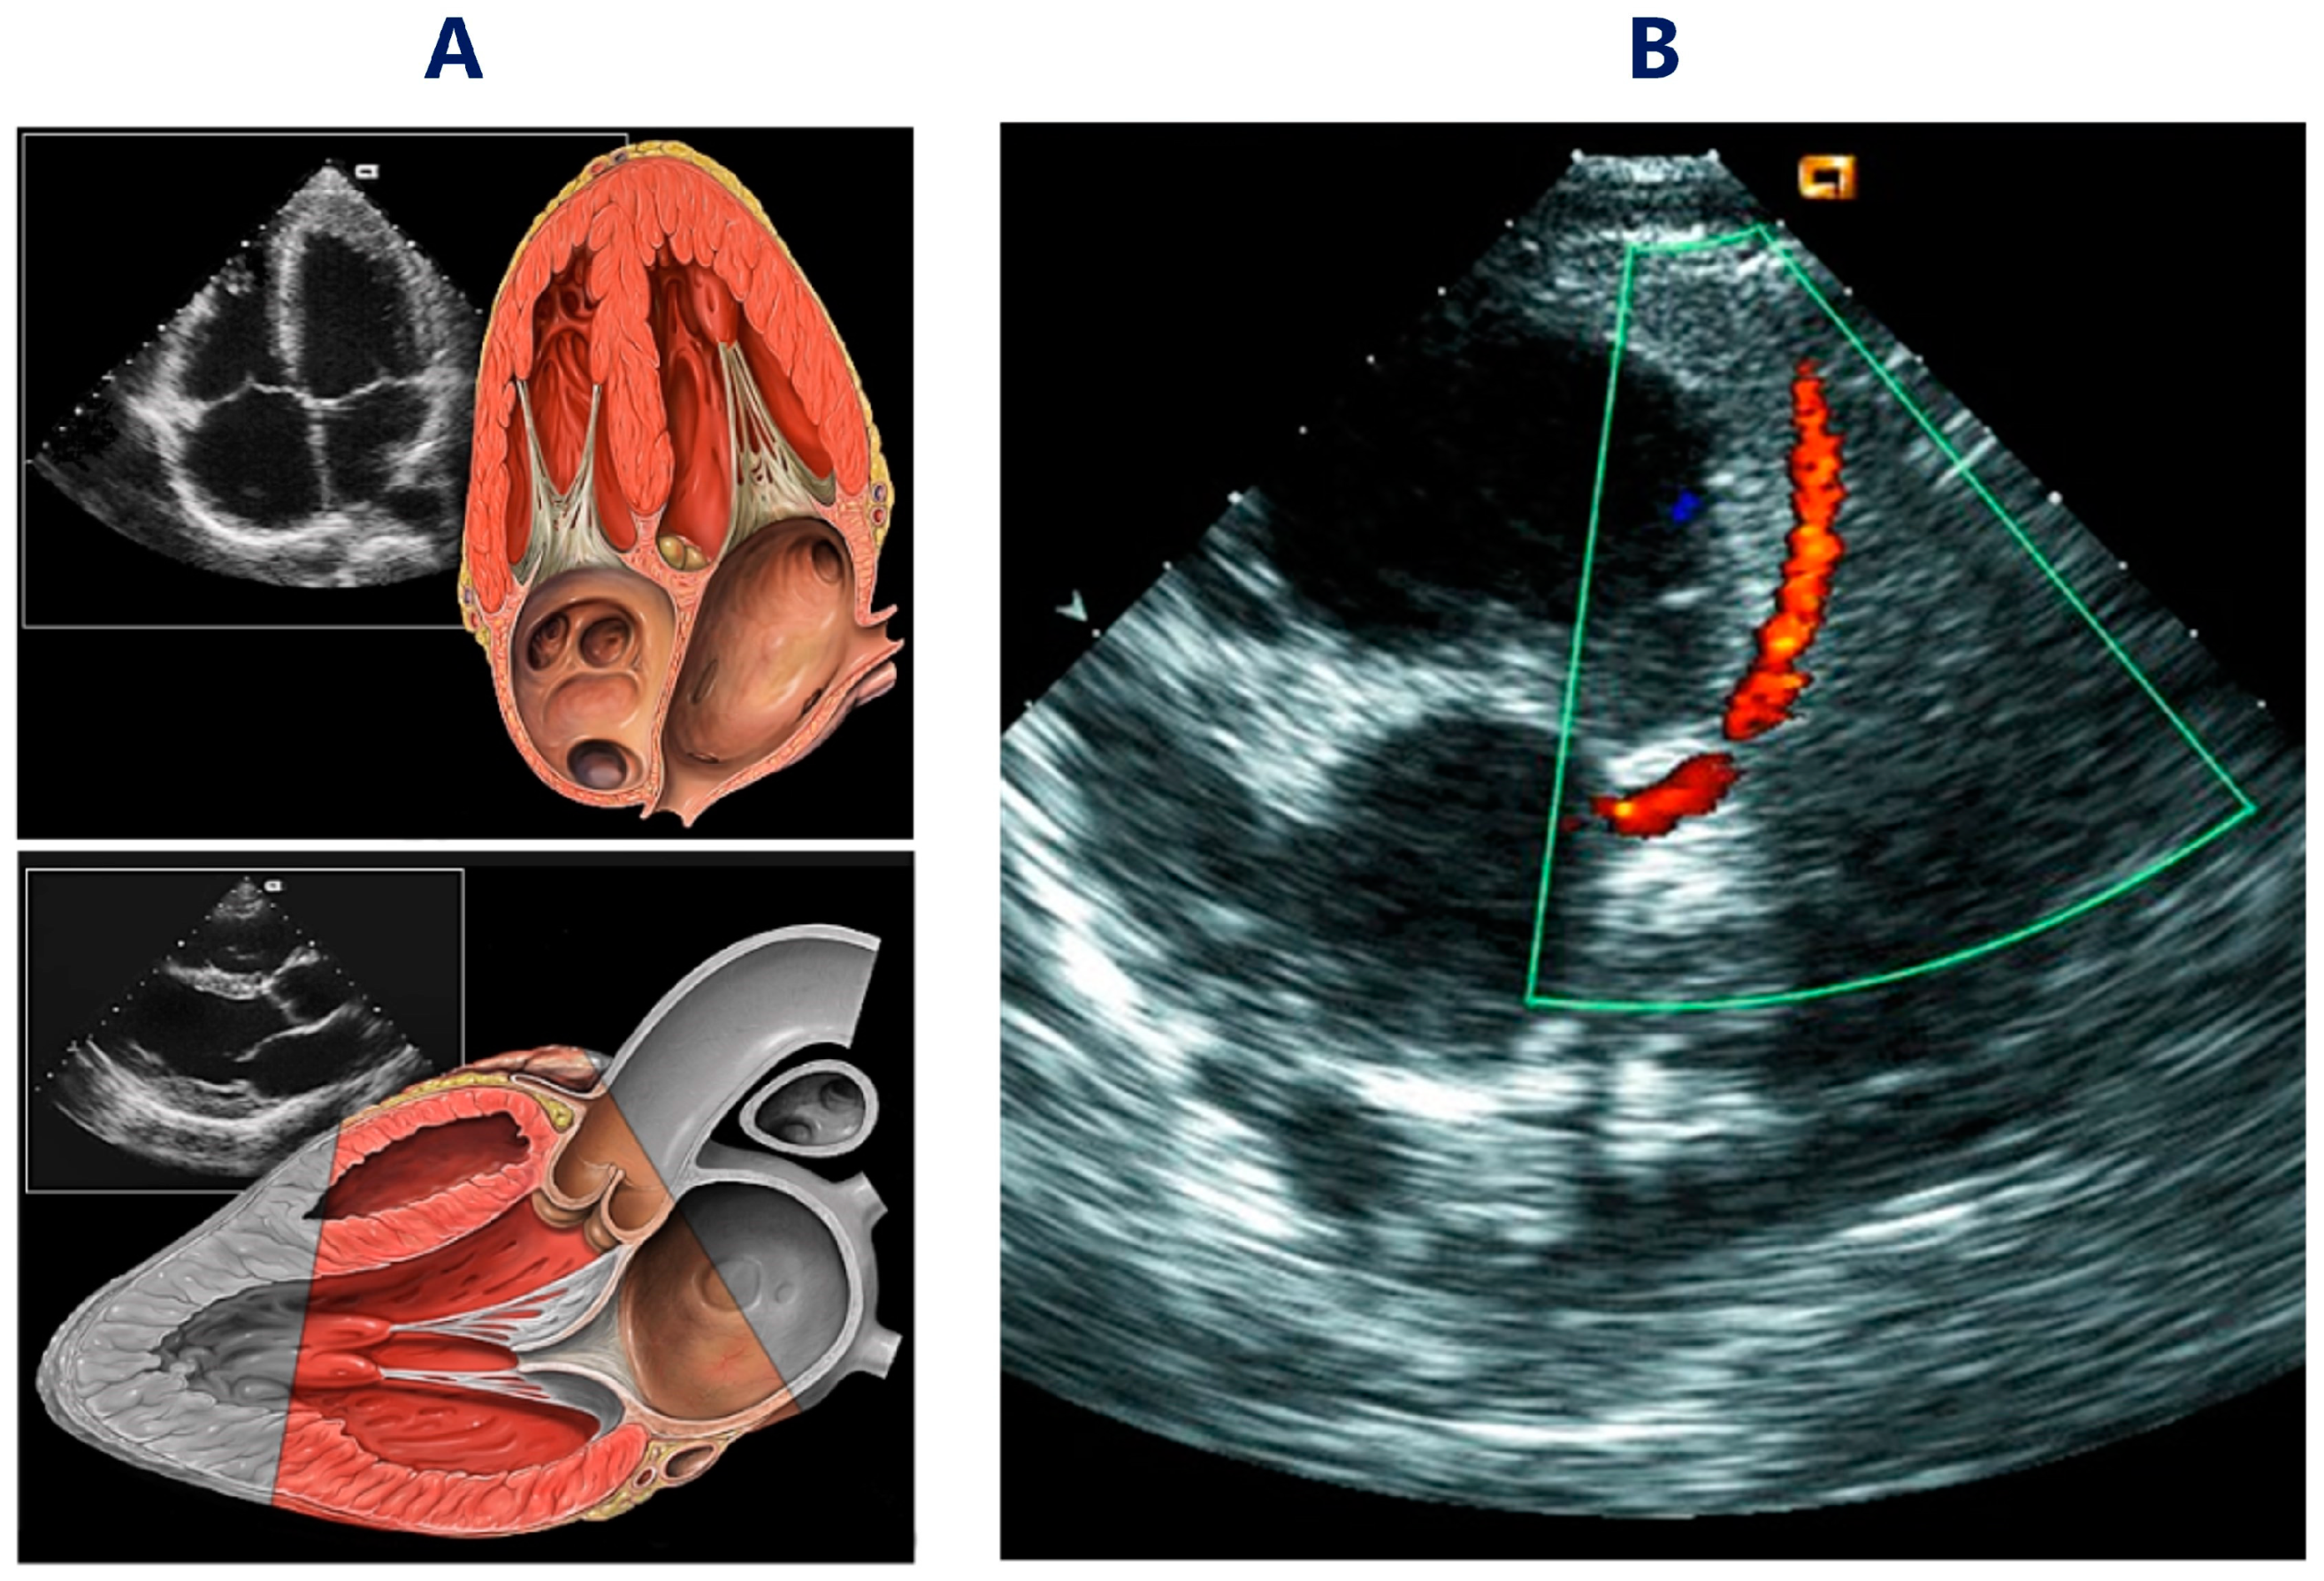

Figure 1 presents two selected heart medical visualizations. The first one is very popular and presents heart muscle on echocardiography images (Figure 1A), but the second is much more difficult to recognize and presents the left main coronary artery in a color-coded, transthoracic Doppler echocardiography (Figure 1B).

Figure 1.

Examples of selected medical visualizations of the heart. (A) Heart muscle, normal transthoracic echocardiography views (Wikimedia Commons License). (B) Doppler visualization of the left coronary artery. (Wikimedia Commons License).

The assessment of the meanings of these two images, as well as their medical interpretations, mainly depend on specialist medical knowledge, but also on experience and expectations related to the content of the assessed images.

Without specialized knowledge of such images, it is impossible to understand what they represent and recognize them correctly. If the observer has certain expectations but does not have specialized knowledge, the observed images can only be assessed in a general way from an aesthetic point of view. This would be the case if they were assessed by people without medical knowledge or by people who were unfamiliar with diagnostic imaging [8]. Their assessment would mainly consist of the assumption that they resemble the structure of the heart muscle. Therefore, most people without medical knowledge recognize the first image from the two images presented in Figure 1 as being typical of the structure of the heart. A slightly different situation occurs when the person assessing the images has specialized medical knowledge and skills in diagnostic imaging. By looking at these images, the person will be able to correctly recognize that both structures represent health problems, even if this person were to be looking at a blurry visualization. Specialized knowledge, without a priori expectations, will enable the correct recognition of the image only if it is easy to interpret, i.e., without any modifications and distortions [9].